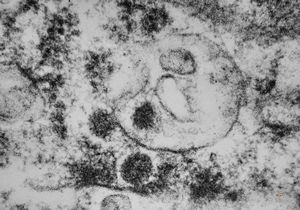

cytomegalovirus - pneumonia